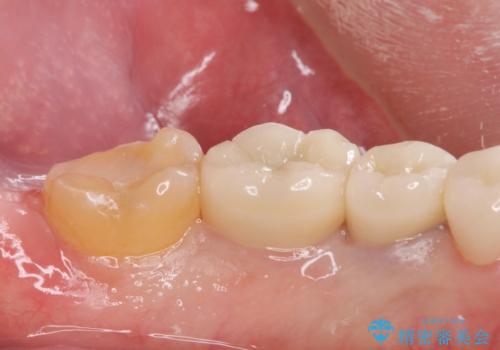

- 過去に治療したゴールドの詰め物が取れて来院。取れたのは2回目だそうです。レントゲンでは適合が良いので再装着可能だったが、

もう取れたくないとの事だったので被せ物のご案内をしました。ゴールドの被せ物の希望だったのでゴールドクラウンでの治療になりました。

適合の良いゴールドクラウンが入りました。

ゴールドは適合が良く、割れる心配もありません。

また、虫歯になるリスクも銀歯と比べて低くなります。